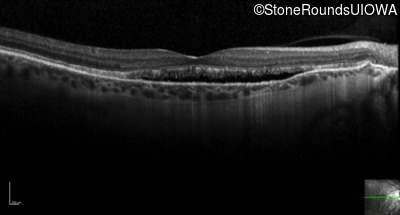

Optical Coherence Tomography - Right - 20/20 -3 sc

Exemplar / OCT Stack

OCT Stack